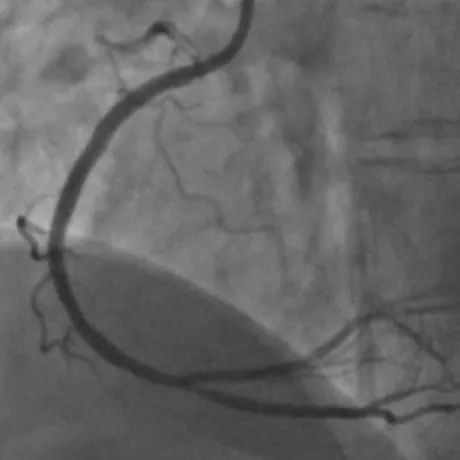

16:00,宋俊贤和张静医生迅速完成导丝通过球囊扩张及支架置入,而此时距离患者发生胸痛仅有60分钟,达到了急性心肌梗死治疗指南中FMC-to-W(首次医疗接触到导丝通过)不超过60分钟的国际标准,时间就是生命,时间就是心肌,及早成功开通梗死的血管是救治急性心肌梗死患者关键所在。

在黄金时间窗内,争分夺秒成功开通闭塞的血管,尽可能多的保护了更多心肌。手术非常成功苏阿姨胸闷、胸痛症状随即消失,术后心电图恢复正常。